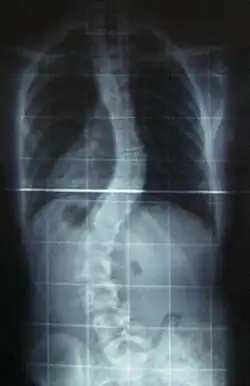

When scoliosis is suspected, weight-bearing, full-spine AP/coronal (front-back view) and lateral/sagittal (side view) X-rays are usually taken to assess the scoliosis curves and the kyphosis and lordosis, as these can also be affected in individuals with scoliosis. Full-length standing spine X-rays are the standard method for evaluating the severity and progression of scoliosis, and whether it is congenital or idiopathic in nature. In growing individuals, serial radiographs are obtained at 3- to 12-month intervals to follow curve progression, and, in some instances, MRI investigation is warranted to look at the spinal cord.[80] An average scoliosis patient has been in contact with around 50–300 mGy of radiation due to these radiographs during this period.[81]

The standard method for assessing the curvature quantitatively is measuring the Cobb angle, which is the angle between two lines, drawn perpendicular to the upper endplate of the uppermost vertebra involved and the lower endplate of the lowest vertebra involved. For people with two curves, Cobb angles are followed for both curves. In some people, lateral-bending X-rays are obtained to assess the flexibility of the curves or the primary and compensatory curves.

Scoliosis is defined as a three-dimensional deviation in the axis of a person's spine.[46][7] Most instances, including the Scoliosis Research Society, define scoliosis as a Cobb angle of more than 10° to the right or left as the examiner faces the person, i.e. in the coronal plane.[86]